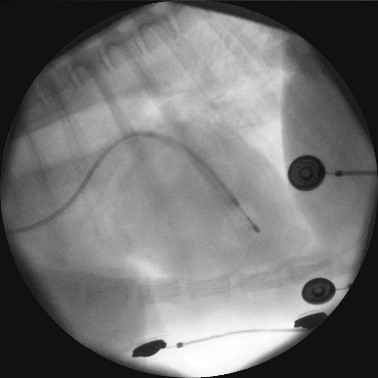

一時ペーシング療法(経食道法、径頸静脈法)

不整脈や心不全の動物を治療している途中で他の病気での手術が必要になる場合があります(骨折、腫瘍、子宮蓄膿症等)。

問題になるのは麻酔による心機能の低下や停止です。

術前の心機能評価を確認いたします。

加えて、心機能低下を未然に防ぐために一時的に体外式ペースメーカーにて心臓の動きをサポートする方法です。

食道や頸静脈にカテーテルを刺して心臓を電気刺激します。

当院では頸静脈ペーシングをお勧めしています。

カテーテル刺入から2-3分でペーシングを開始、術後麻酔終了時又はICU離脱時に抜去いたします。

PCで心拍数を維持するだけではなく拍出量も補助できます。